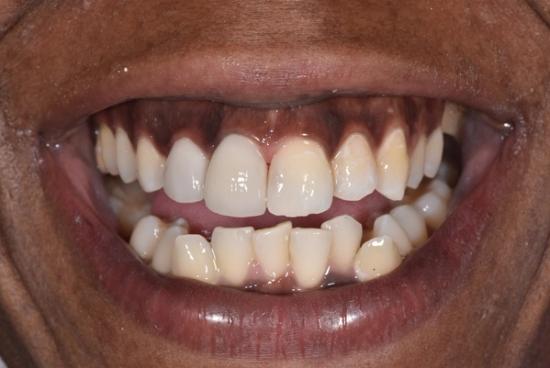

After Photo